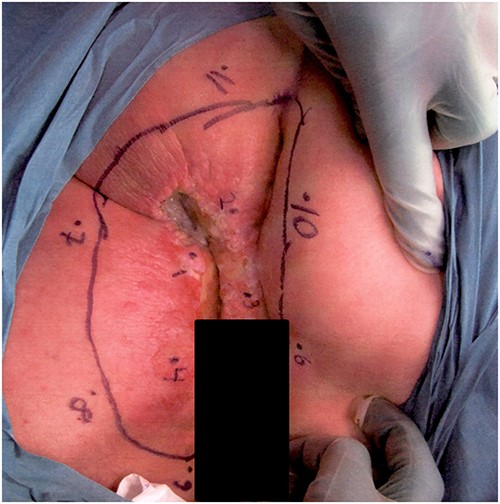

An 84-year-old man with a history of hypertension, hyperlipidemia, sleep apnea, and an earlier transient ischemic attack was referred with a history of itching and bleeding for 6 months from a perianal rash. The lesion was 5 × 6 cm, with a central ulceration of 2 × 2 cm (Fig. 2). Histopathological examination showed Paget in one biopsy and Paget with underlying anal gland carcinoma in the other. At a multidisciplinary conference, the lesion was interpreted as adenocarcinoma from the cryptal glands of the anal canal, secondary to the Paget.

Photograph of the lesion in our second patient. Biopsies confirming Paget’s disease in biopsy marked 1 and Paget with underlying anal gland carcinoma in biopsy marked 2.

Rigid sigmoidoscopy visualized a 3 mm adenoma and hemorrhoids, but was otherwise normal. CT thorax-abdomen showed bladder diverticula but no metastases. An MRI of the rectum presented a superficial tumor and a 13-mm pathological lymph node in the right groin. PET-CT confirmed pathological metabolism in the right groin but no other signs of metastases. The patient was treated with long-course RT (45 Gy/25 fractions) combined with capecitabine. At reevaluation 1 month later, no visible tumor could be seen. MRI of the rectum showed regress and no suspect glands in the groin, and FDG-PET-CT showed complete metabolic regression in the perianal area and in the right groin. At the revisit 3 months later, no visible tumor could be seen, and FDG-PET-CT was performed without signs of relapse. Unfortunately, the patients developed liver and skeletal metastases from the anal gland carcinoma after 21 months and died 3 months later.